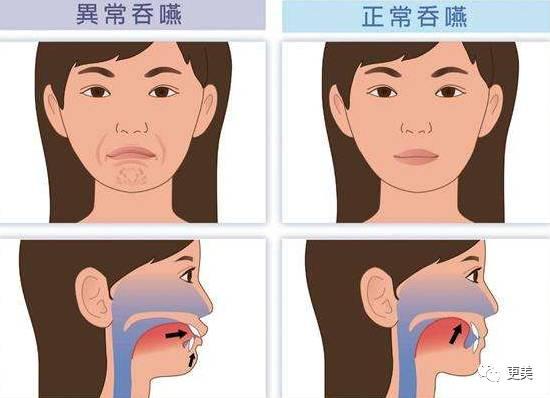

正确的吞咽应该是舌肌发力,也就是只有喉咙在动,你的脸颊、下巴、嘴唇都不会跟着动的,吞咽的时候舌头用力的顶住上颚

动起来大概就是这样~妹子们可以喝杯水或者咽吐沫试一下,感受自己吞咽时的状态,你的舌头是否顶住了上颚?

而不良的吞咽习惯是吞咽的时候,舌头总是会不自觉地顶住门牙,而长期下去形成的龅牙,有研究指出:舌头对牙齿的推力超过五百公克就相当于半公斤的力量,而每天如果吞咽2000次左右的话,每次推力超过0.5秒,就等于舌头每天在20分钟的吞咽时间内,对牙齿实施了超过1000公斤的推力

用这么强大的力道来推门,门都受不了吧?更可况你的牙了~~所以有不良吞咽习惯的人,尤其是小孩子,门牙会被舌头的推力一直向外长,很容易变成龅牙~~此时嘴唇下方的颏肌也会反推下门牙,让下门牙往内倒,而门牙位置变化后,就会发生下颌后缩